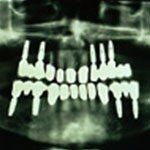

Auf dieser Röntgenaufnahme ist deutlich zu erkennen, wie die Implantate im Kiefer verankert sind.